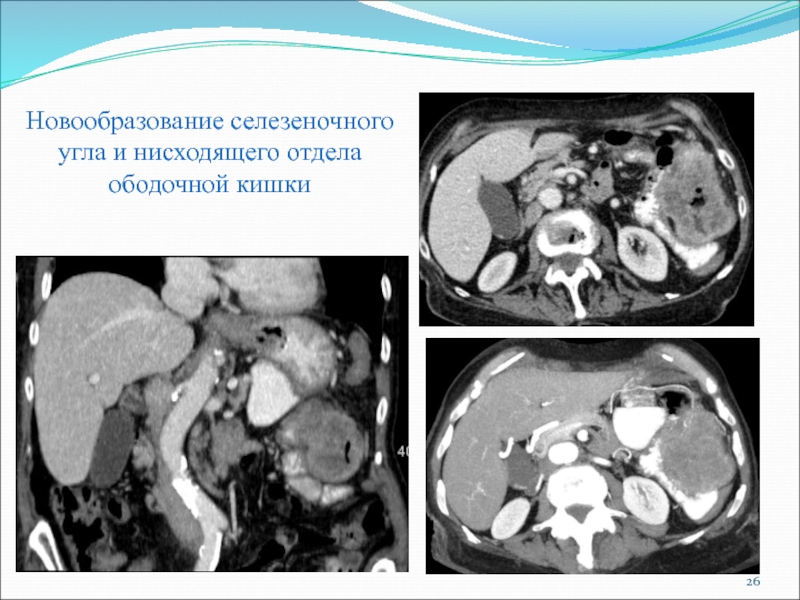

Слайд 26Новообразование селезеночного угла и нисходящего отдела ободочной кишки

Новообразование селезеночного угла и нисходящего отдела ободочной кишки